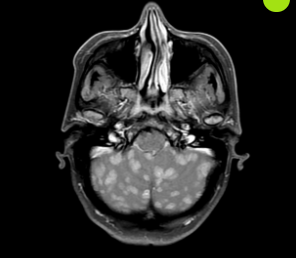

It's Christmas, and your grandfather takes out his famous "pitorro de coco" that has been marinating for the last 10 years. After one too many shots, he starts to present with an acute headache, nausea, and visual changes. His Brain MRI shows the following findings. Looks like grandpa's pitorro gave him this disease.

What is methanol poisoning?